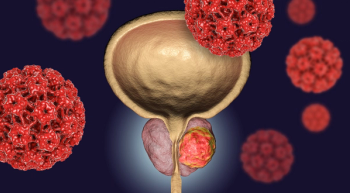

Patient-reported outcomes showed that health-related QOL stayed at baseline for patients with HRRM-positive mHSPC receiving a niraparib regimen.